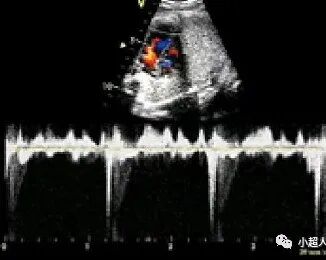

正常M型超声心房波起始部至心室波起始部间距或频谱多普勒A-V间距(相当心电图P-R间期)<150ms

一度房室传导阻滞频谱多普勒A-V间距>150ms(取样容积可左室流入-流出道区,上腔静脉和升主动脉相邻区,下腔静脉和腹主动脉相邻区,肺动、静脉相邻区--动脉代表室率)